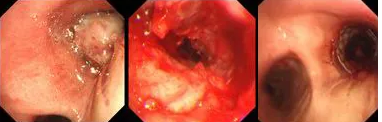

氣短、胸悶、呼吸困難,80歲的患者秦爺爺已經(jīng)出現(xiàn)了瀕死癥狀;局麻、右主支氣管再通,僅用6秒,胸科專(zhuān)家順利實(shí)施TTS氣道支架手術(shù)。

原來(lái),秦爺爺入院時(shí)診斷為“右主支氣管”鱗狀細(xì)胞癌伴壞死。他的右主支氣管被腫瘤完全堵塞,混合性狹窄。面罩吸氧10升/分的狀況下,指脈氧只有85%,無(wú)法平躺,呼吸困難,病情十分危急,隨時(shí)有生命危險(xiǎn)。

經(jīng)評(píng)估并與家屬溝通同意后,歐陽(yáng)海峰副院長(zhǎng)決定為患者實(shí)施TTS氣道支架手術(shù)。手術(shù)當(dāng)天,在麻醉手術(shù)中心的配合下,歐陽(yáng)海峰副院長(zhǎng)為患者在局麻下快速凍切腫瘤組織,實(shí)現(xiàn)右主支氣管再通,并經(jīng)氣管鏡活檢孔道迅速植入14*30 TTS支架一枚。支架植入過(guò)程耗時(shí)僅6秒,迅速緩解了患者的氣短瀕死癥狀。